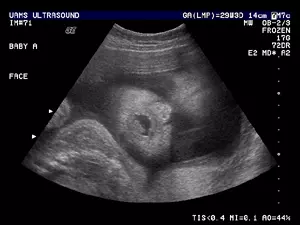

V naši ambulanti se vedno trudimo imeti čimbolj strokoven pristop. To lahko dosežemo le z nenehnim izobraževanjem in spremljanjem razvoja medicinskih postopkov doma ter v tujini. Tako smo se med drugim specializirali za različne preglede, kot je nuhalna svetlina Ptuj.